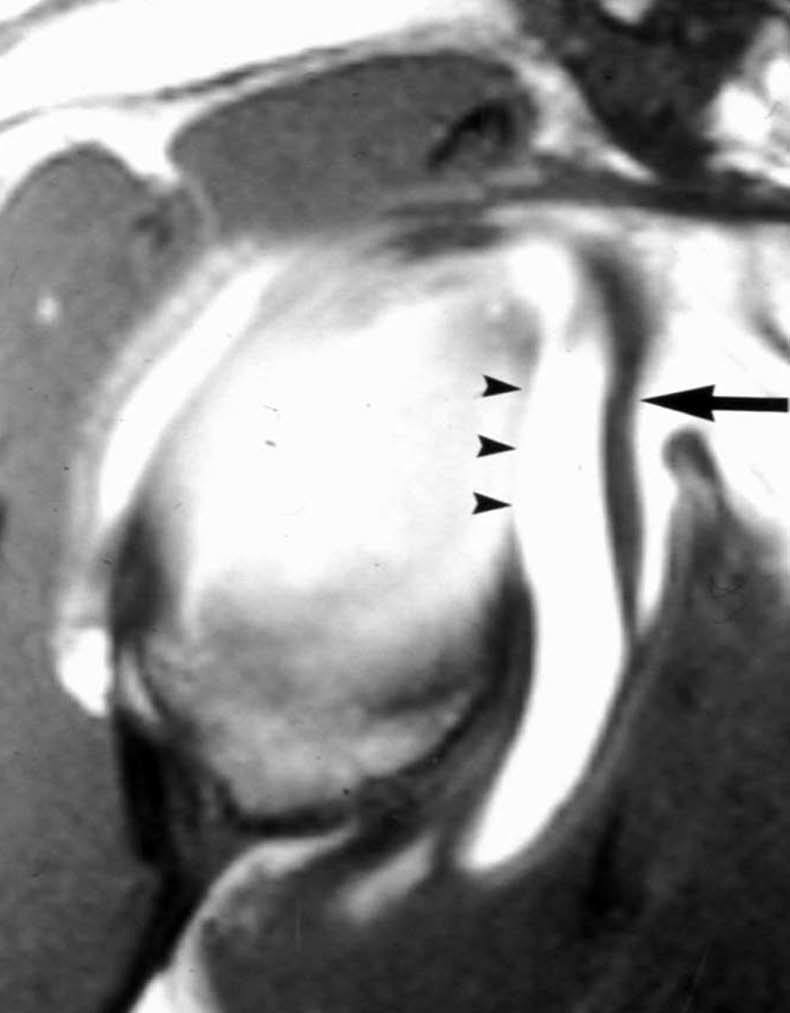

POLPSA (posterior labral periosteal sleeve avulsion)

Esta lesión se asemeja a la ALPSA, pero ocurre en el borde glenoideo posterior. El LG se halla desplazado hacia dentro y por detrás del borde glenoideo posterior. El mecanismo de producción del POLPSA es una dislocación posterior, y por tanto se puede encontrar también un Hill Sachs invertido19 (fig. 14).

. Artrorresonancia axial T1 con supresión grasa donde se observa una rotura del labio glenoideo posterior con desplazamiento posteromedial (flecha). Nótese la situación del labio glenoideo en comparación con una rotura sencilla, no desplazada, que se observa en la figura 13. Obsérvese la presencia de una lesión de Hill-Sachs invertida (cabezas de flecha), en relación con una dislocación posterior con reducción.Lesión de Bennett